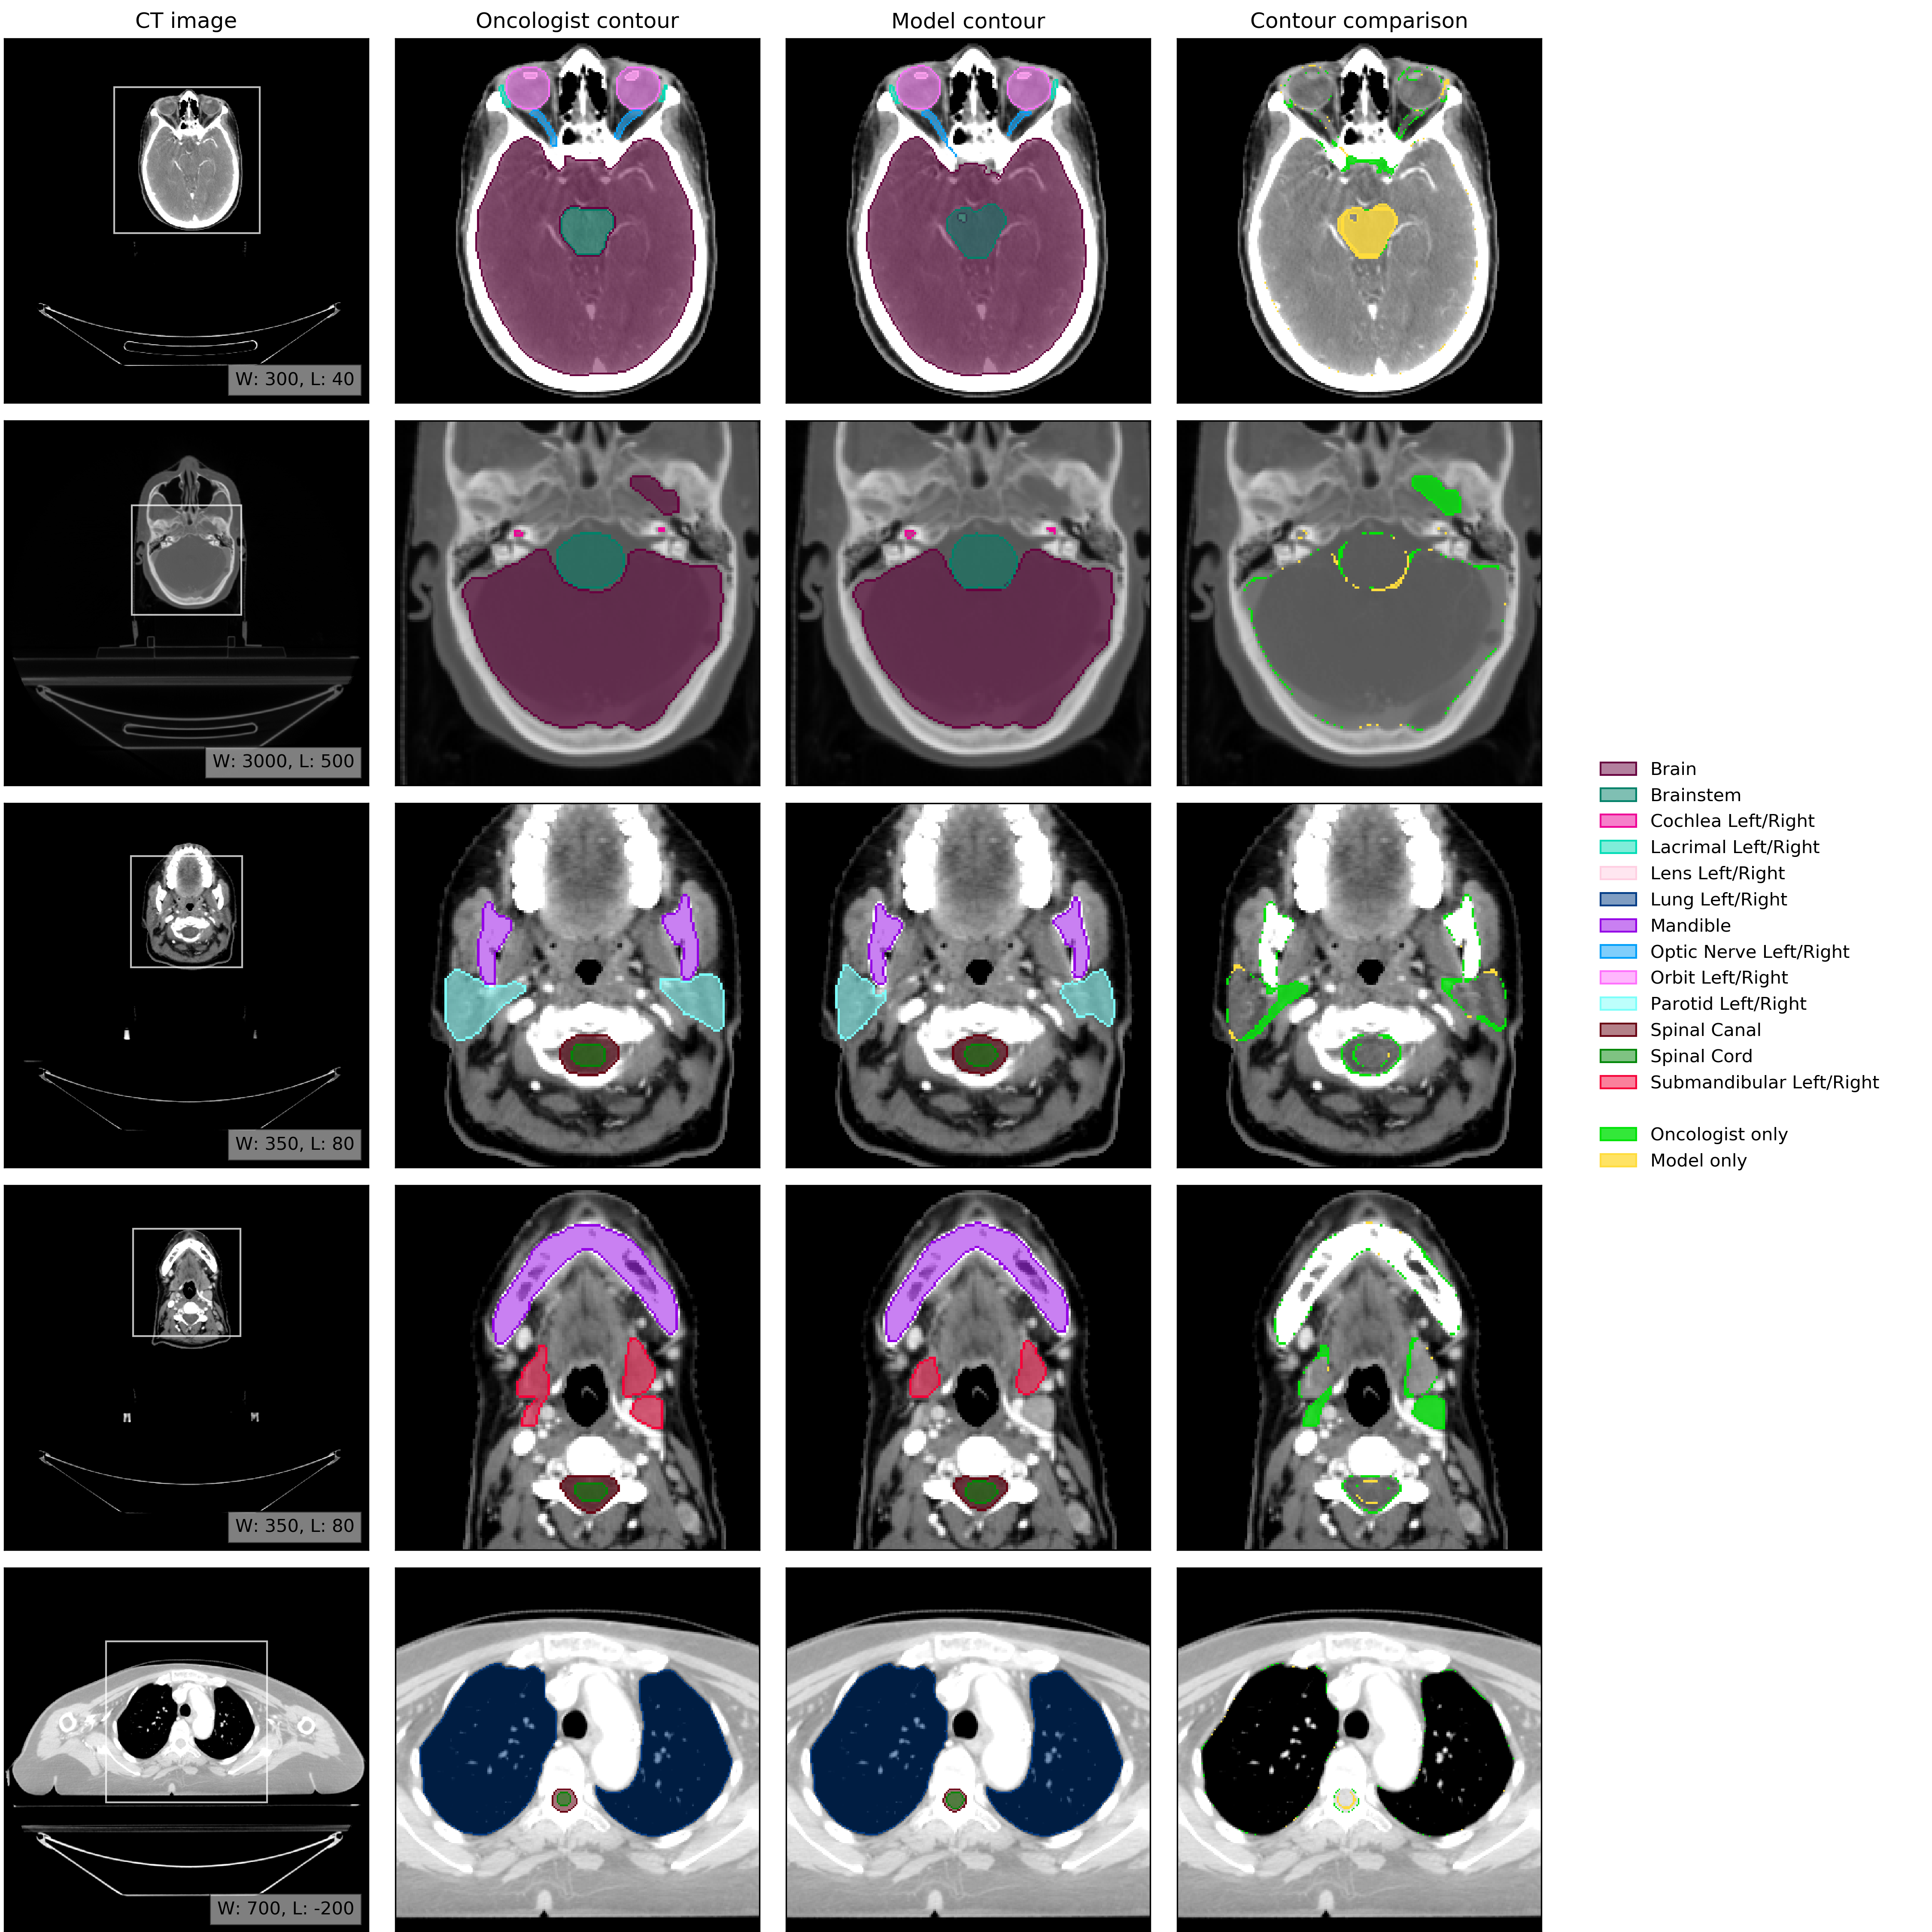

An example of model performance is shown in Fig. 2. We compare our performance (model vs oncologist) to radiographer performance (radiographer vs oncologist). For more information on dataset selection, inclusion and exclusion criteria for patients and OARs please refer to the Methods section.

Refer to caption

Figure 2: Example results. (CT image) Axial slices at five representative levels from the raw CT scan of a 55-59 year old male patient was selected from the UCLH dataset (patient UCLH-20) were selected to best demonstrate the OARs included in the work. The levels shown as 2D slices have been selected to demonstrate all 21 OARs included in this study. The window levelling has been adjusted for each to best display the anatomy present. (Oncologist contour) The ground truth segmentation, as defined by experienced radiographers and arbitrated by a head and neck specialist oncologist. (Model contour) Segmentations produced by our model. (Contour comparison) Contoured by Oncologist only (green region) or Model only (yellow region). Two further randomly selected UCLH set scans are shown in Fig. 12 and Fig. 13. Best viewed on a display.